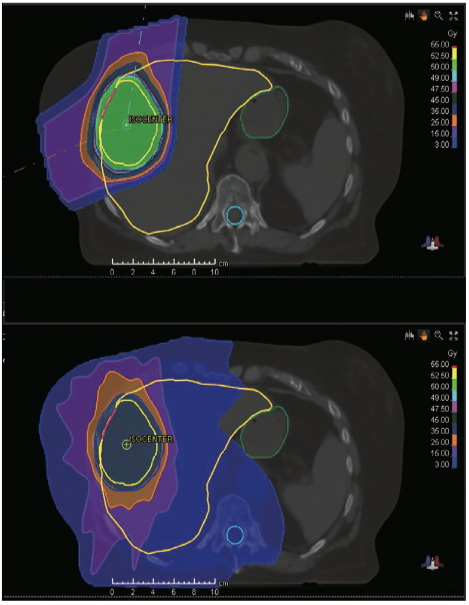

81岁女性,晚期HCC的CT图像,IVC中可见大量肿瘤血栓。PBT前(a)、PBT期间(b)、PBT完成后2个月(c)的CT图像。PBT后,肿瘤和肿瘤血栓均显著消退(箭头)。等高线:红线,等剂量为90%;蓝线,等剂量为10%。HCC,肝细胞癌;IVC,下腔静脉;PBT,质子治疗。(图片来自参考文献2)